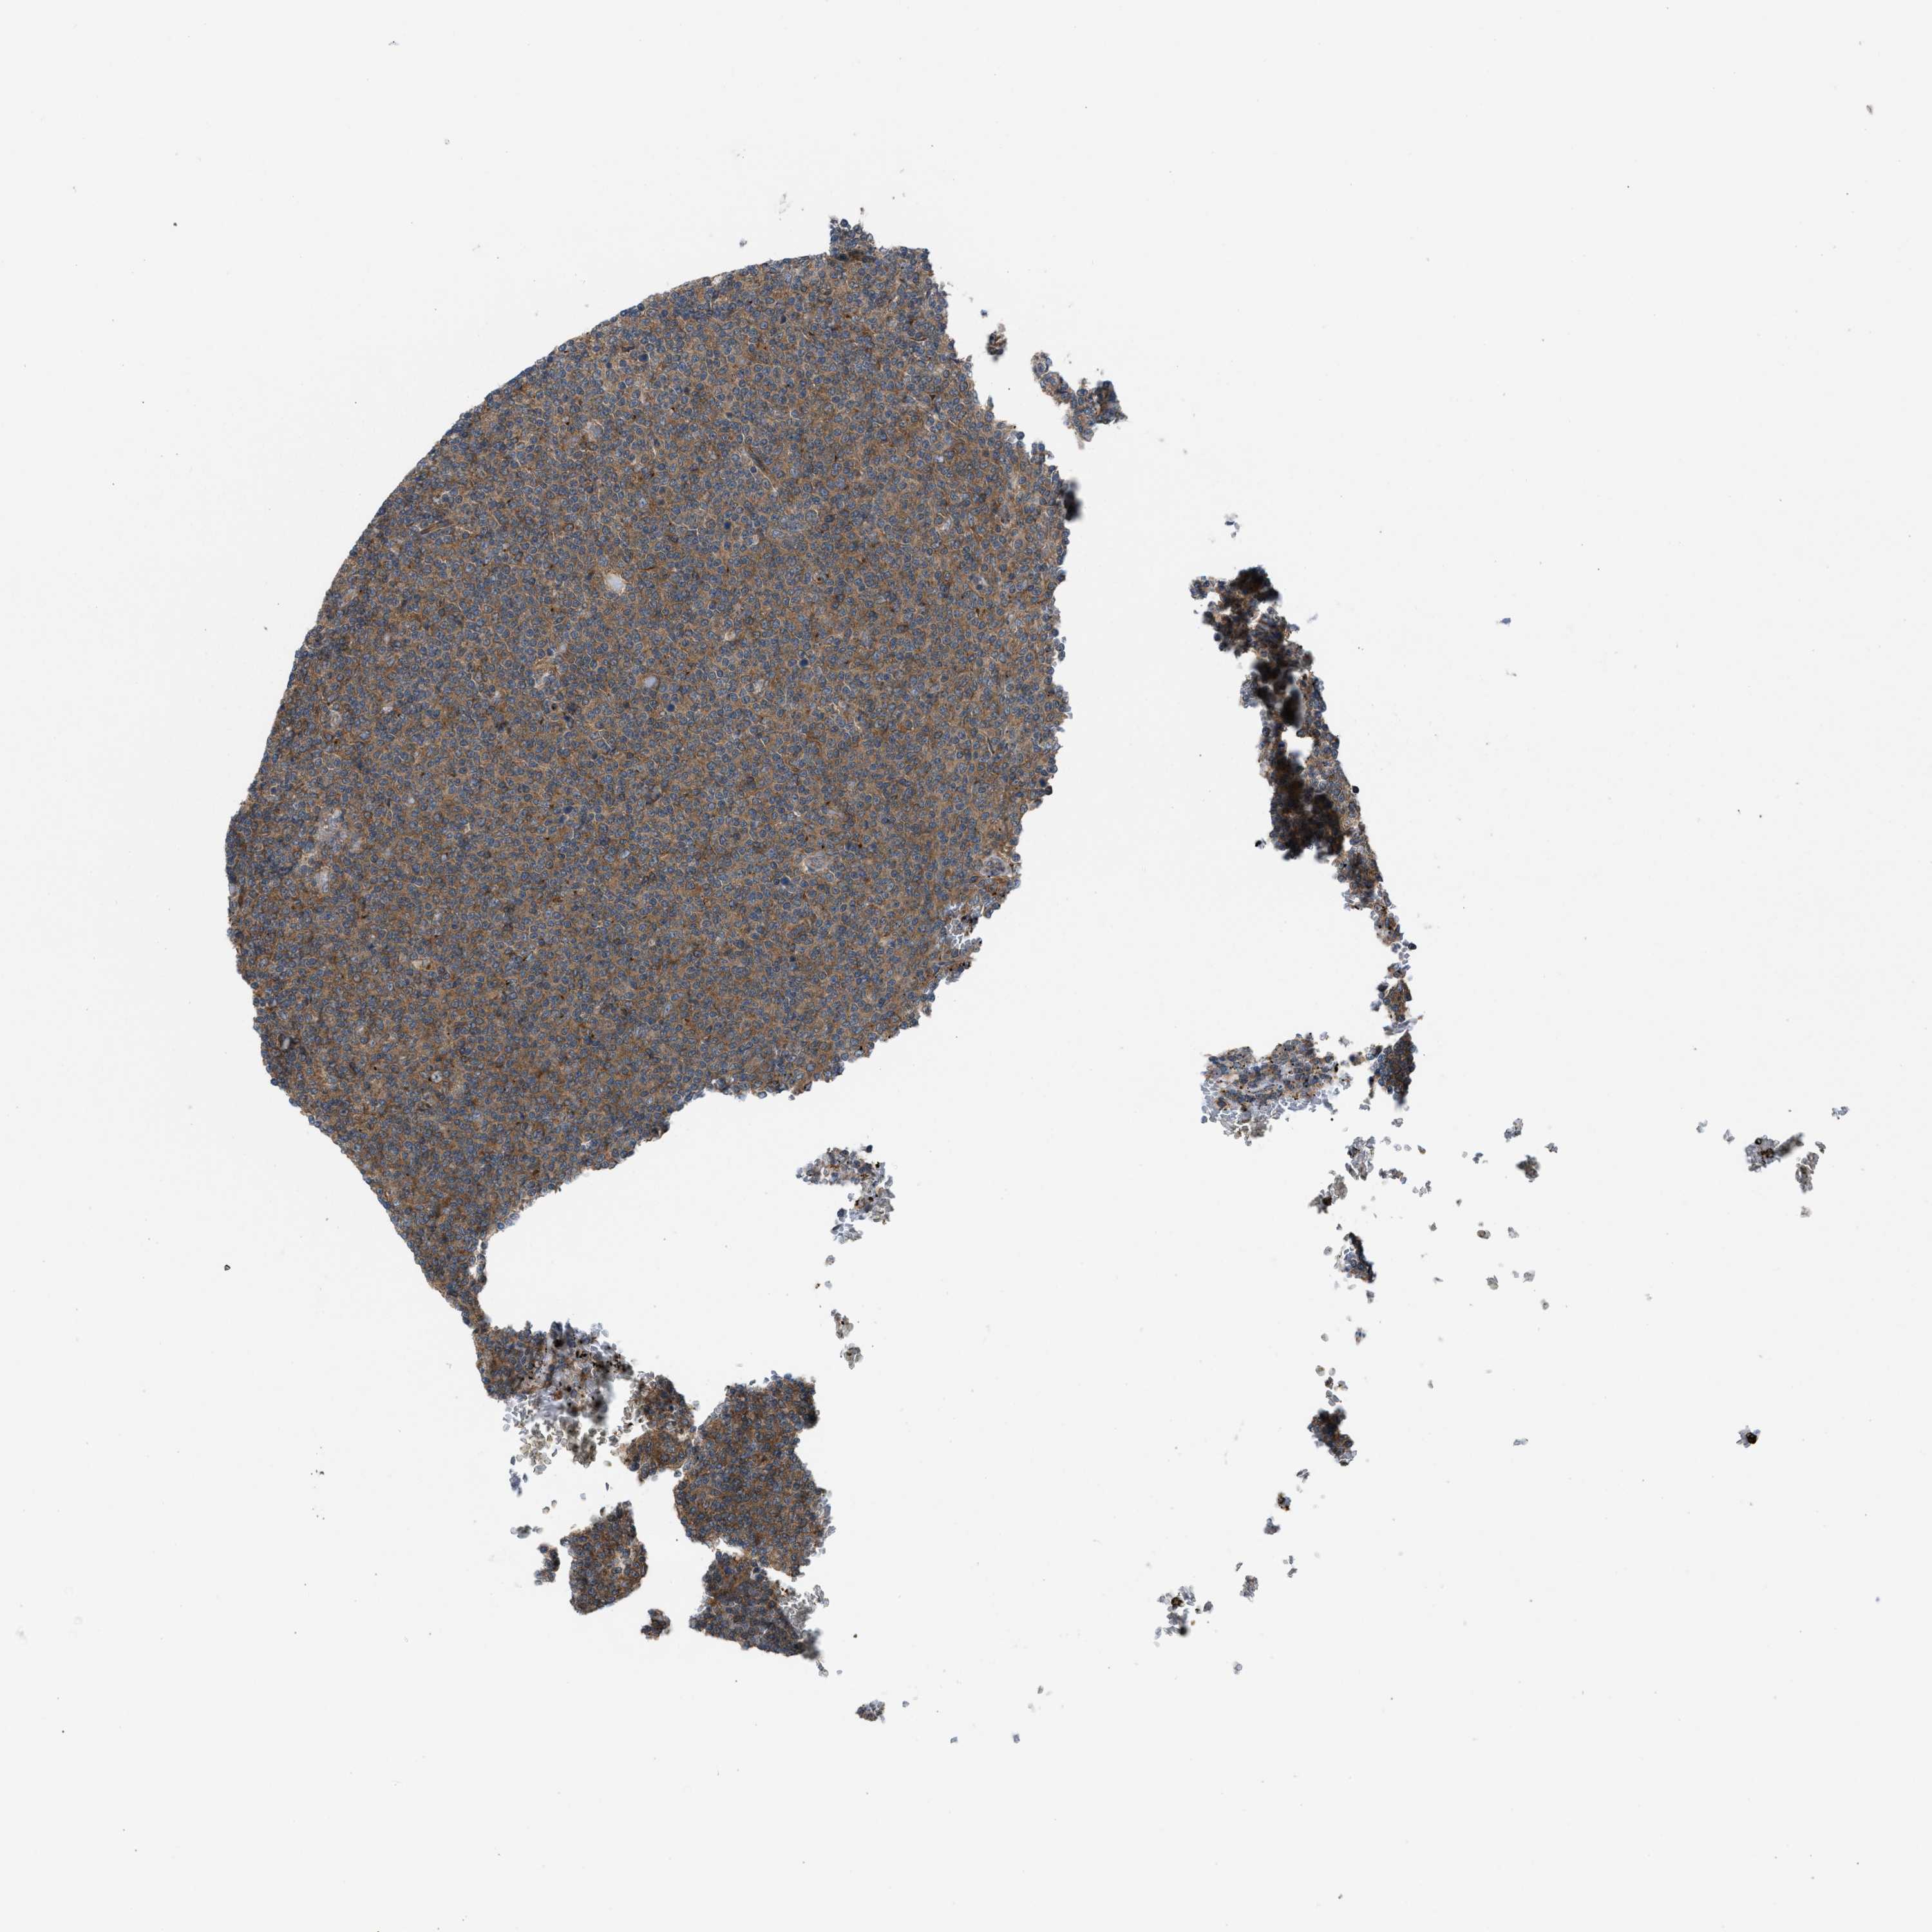

LYMPHOMA - Protein expressioni

A mouse-over function shows sample information and annotation data. Click on an image to view it in a full screen mode. Samples can be filtered based on level of antibody staining by selecting one or several of the following categories: high, medium, low and not detected. The assay and annotation is described here.

Antibody staining in the annotated cell types in the current human tissue is reported as not detected, low, medium, or high, based on conventional immunohistochemistry profiling in selected tissues. This score is based on the combination of the staining intensity and fraction of stained cells.

Each image is clickable and will lead to virtual microscopy that enables deeper exploration of all samples and also displays staining intensity scores, fraction scores and subcellular localization as well as patient and tissue information for each sample.

Antibody HPA021197

Hodgkin's disease, NOS